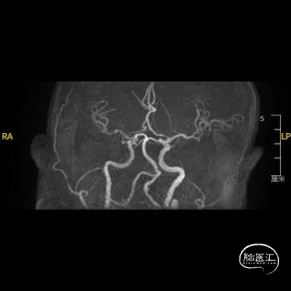

➢ 脑血管造影检查

患者主因言语不利3天入院,头核磁提示右侧额、顶叶多发低灌注梗塞,脑血管造影提示右侧颈内动脉开口重度狭窄,为责任血管,另外患者前交通动脉、右侧后交通动脉开放不良,并且狭窄严重,考虑到高灌注风险,决定分期处理,一期小球囊扩张改善供血,二期支架成型。